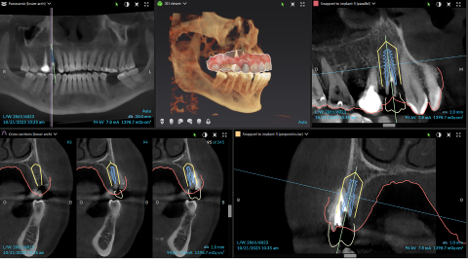

3D X-rays, also known as CBCT imaging, provide a highly detailed, three-dimensional view of your teeth, jaw, and surrounding structures, offering far more clarity than traditional 2D X-rays. Using a cone-shaped beam that rotates around your head, the scanner captures multiple images in under a minute. It compiles them into a comprehensive digital model of your oral anatomy.

This enhanced level of detail improves diagnostic accuracy, helps detect hidden issues, and enables precise planning of complex treatments, such as implants, orthodontics, and surgical procedures. Patients benefit from more customized care, reduced surgical time, and lower radiation exposure, making 3D X-rays a safe and valuable tool in modern dentistry.

X-Guide Navigation: GPS-Guided Implant Surgery

X-Guide Navigation is an advanced technology that brings GPS-like precision to dental implant surgery, offering real-time guidance for the most accurate placement possible. The process begins with a detailed 3D scan that allows the dentist to digitally plan the ideal implant position, angle, and depth before the procedure even starts.

During surgery, the system tracks surgical instruments in real-time and provides instant visual feedback, allowing the dentist to follow the plan precisely while making adjustments as needed. This level of accuracy leads to shorter procedures, greater surgical confidence, reduced risk of complications, and highly predictable, long-lasting implant results.